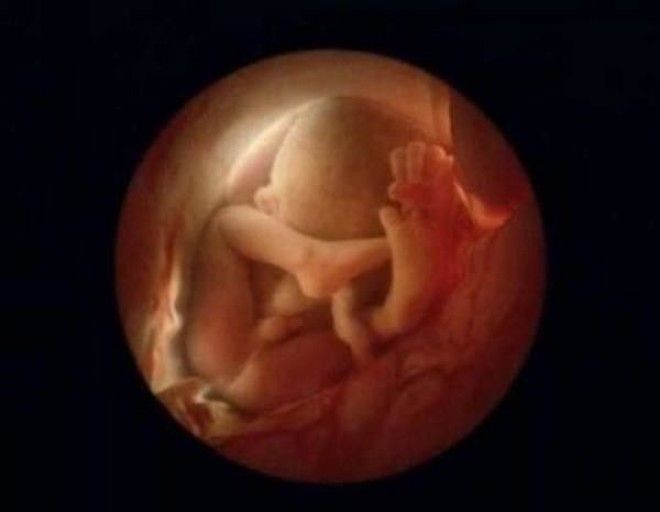

10 недель. Малыш уже использует руки для изучения окрестностей

16 недель